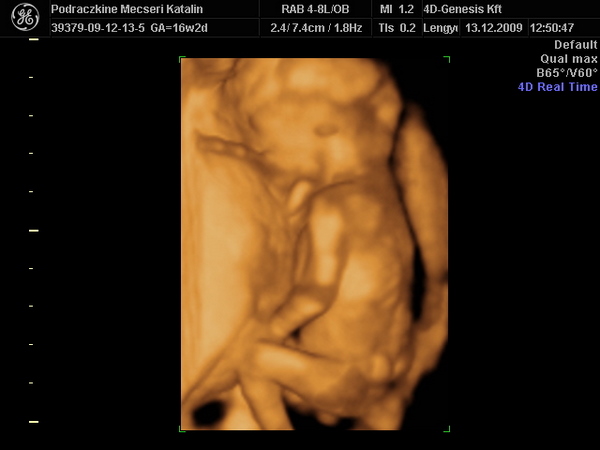

Újabb pasi érkezik Kolos. :D

16 hetesen ilyen. :wink: